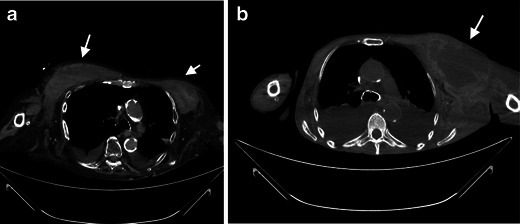

Figs. 1 and 2.

A 43-year-old female patient with a newly placed central venous catheter. Non-contrast CT of the upper thorax with axial reconstruction illustrates unsuccessful catheter implantation with a space-occupying lesion in the left and right chest wall (white arrows), which is partly solid, as seen with haematoma